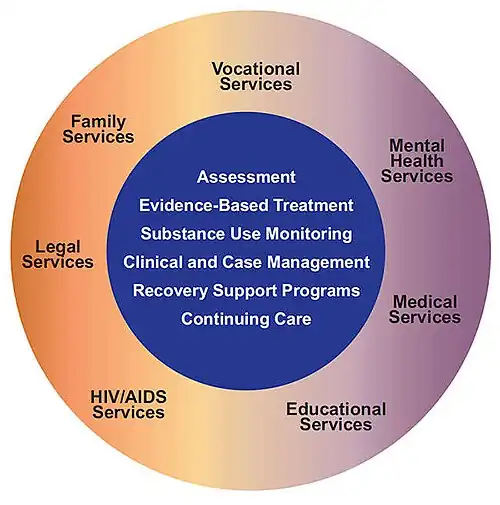

Substance Use Disorder (SUD) is understood as the persistent use of substances to the detriment of the individual's livelihood and wellness. SUD can have serious mental, physical, and social ramifications if not properly addressed. Though SUD can develop at any age, it is especially important to address in adolescents, given rising prevalence of certain substances (e.g. cannabis) in that age group and poor prognosis associated with early-onset SUD. Data from the National Survey on Drug Use and Health show the lifetime use of illicit drugs in people ages 12-17 is 20.9%. The same survey found the rate of Substance Use Disorder in the past year for people ages 12-17 who used illicit drugs or alcohol to be 6.3% in 2020. [...] This paper is intended for clinicians and lay people to gain a deeper understanding of SUD in adolescents, particularly relating to alcohol, cannabis, nicotine, and opioids. Though alcohol, cannabis, and nicotine are the substances most commonly used by this age demographic nationally, opioid use – and resulting deaths – have been on the rise. According to the Centers for Disease Control and Prevention (CDC), opioids were connected to about 75% of the nearly 92,000 drug deaths in 2020. Beyond significant death rates in the general population, recent spikes in adolescent death rate tied to the synthetic opioid fentanyl – which held a relatively stable death rate from 2010 to 2019 until seeing a 94% increase from 2019 to 2020 and additional 20% increase to 2021 - warrants inquiry into opioids for this population. Each of these substances can have adverse, long-lasting effects on health if not managed properly, resulting in seriously compromised lifelong wellbeing. This article explores SUD prevalence and reviews diagnostic criteria in relation to adolescence, including a synopsis of changes in SUD classification between the DSM-IV and DSM-5 and discussion of ICD-11 and the Research Domain Criteria (RDoC) as a basis for research related to substance use. Effective assessment and consideration of co-occurring disorders are covered as well. Although the prognosis of SUD varies by an individual's environment and circumstances, a modal developmental course for SUD is discussed. Finally, a curated list of nationally recognized resources including hotlines, treatment locators, informational sites, and support groups is provided, along with tools to compile local resources. By addressing these aspects of adolescent SUD, the research team offers a broader view of its prevalence in the United States, key warning signs and comorbidities, and possible assessments and treatments for adolescents with SUD. doi: 10.15347/WJM/2023.001